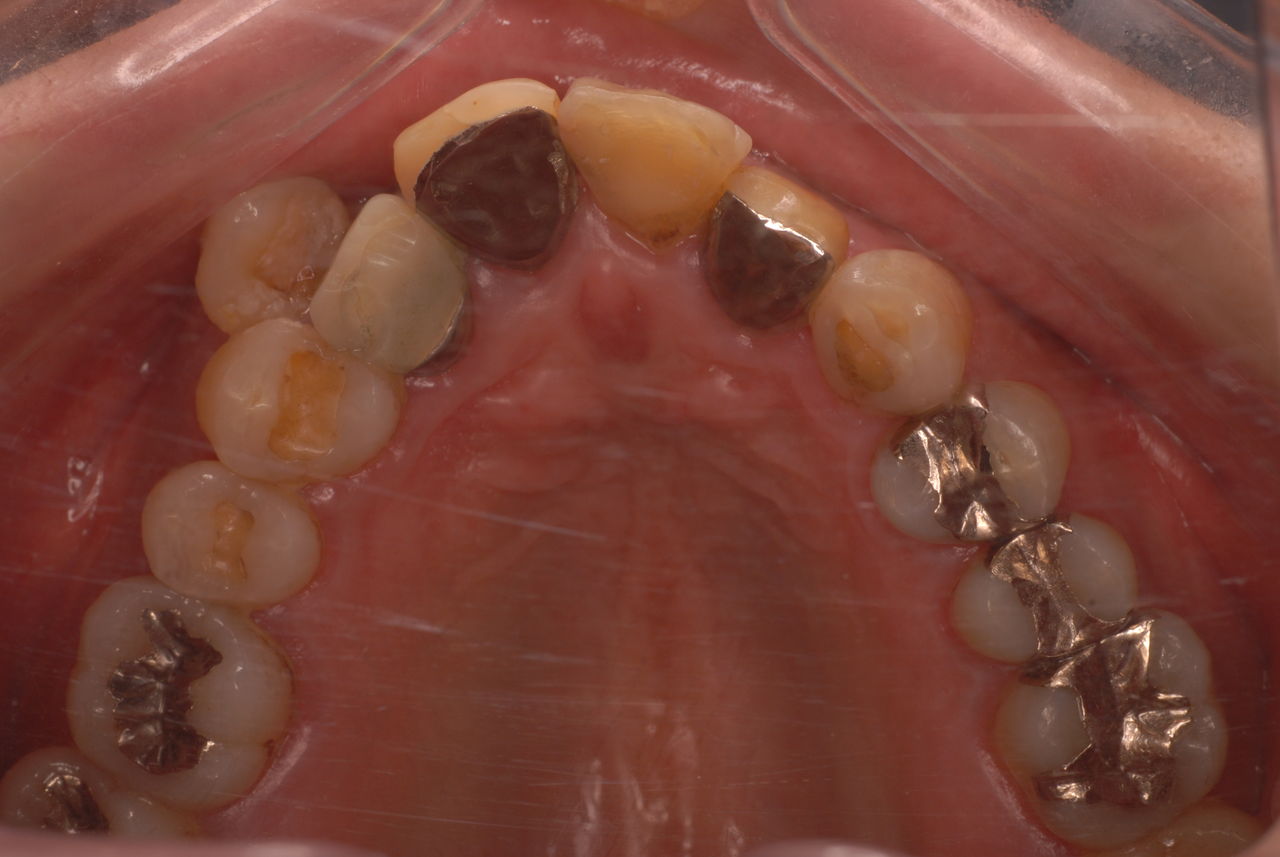

これが歯や顎をいじったり、長期にマウスピースを装着していると絶望的になります。

歯をいじられ体も心もボロボロになった患者さんからの手紙です。マスコミや権威などがいかにいい加減かわかります。歯は触らないほうがよろしいのです。

そもそも歯を触り何らかの金属やセラミックを入れる行為そのものが医学的には傷害処置ですから、なるべく避けるべき物なのです。